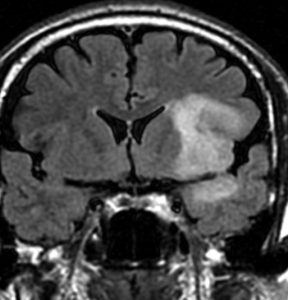

若い女性の左前頭葉から島回,側頭葉を侵す腫瘍で,てんかん発作で発症し,開頭生検 biopsy しました。

一部で,細胞密度が高く,核の腫大とクロマチンの増量,核間距離の短縮があり,核分裂像が認められ,MIB-1染色率が10%です。組織学的には退形成性乏突起膠腫グレード3とされました。

IDH変異あり,1P/19q欠失あり,ATRX変異なしです。

乏突起膠細胞系グリオーマなので,放射線治療の高線量領域はあまり広くとりません。

IMRT Simultaneous Integrated Boost (SIB)で,FLAIR高信号の領域に54グレイ27分割,周囲仮定浸潤領域 generous local areaに46グレイを照射しました。

テモゾロマイド75mg/m2を併用しています。

左の画像は放射線治療直後のMRIですが,すでに腫瘍の縮小がみられます。

テモゾロマイドの維持療法は,24コース 2年間行い,それ以降は無治療としました。

照射後7年の画像です。腫瘍は縮小したまま,患者さんは無症状で経過しています。